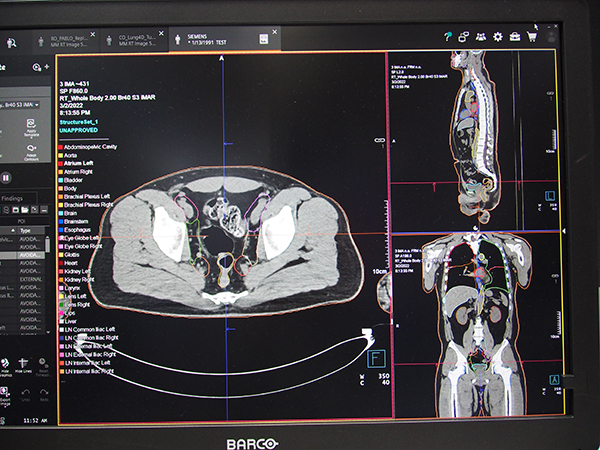

また,放射線治療計画支援システム「syngo.via RT Image Suite」では,治療計画における臓器の輪郭描出(コンツーリング)を自動化する“Deep-learning based Auto Contouring”を利用でき,時間と手間の掛かる作業を大幅に削減できる。頭頸部,胸部,腹部,骨盤部などの87の臓器に対応している。CT撮影後にデータを受け取ると自動で処理が行われ,処理後のデータは放射線治療計画装置に自動転送され,スムーズなワークフローを実現する。今後は,治療計画システムと治療システムを統合する開発を進めていく予定で,放射線治療ワークフローのさらなる最適化が期待される。

自動で高精度な臓器の輪郭描出(コンツーリング)が可能な“Deep-learning based Auto Contouring”